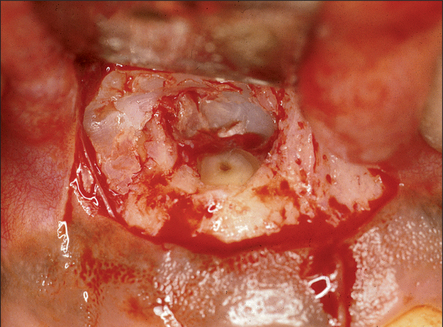

image

Fig. 6.3 A flap has been raised here, exposing a lack of labial bone, which reduces the chances of success for surgical endodontics.